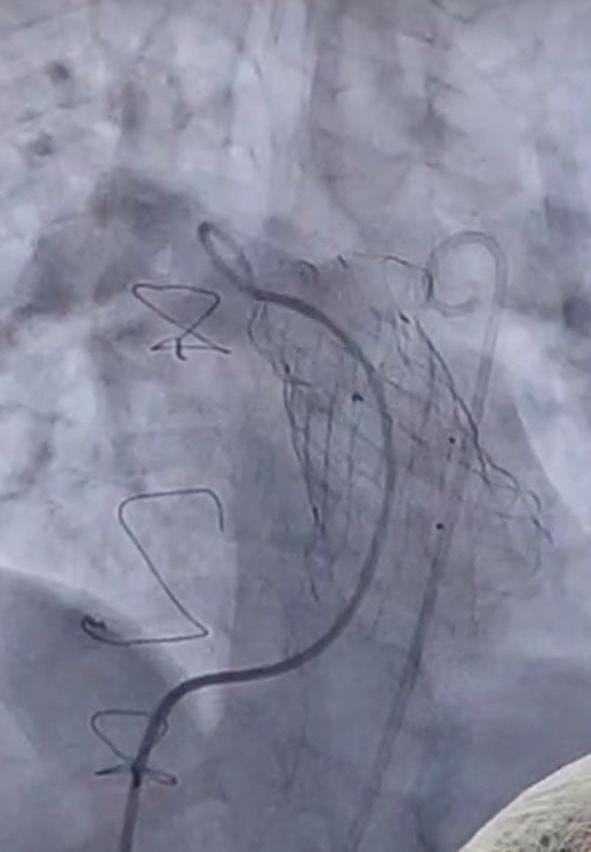

السبت، 05 يوليو 2025 11:12 صأعلنت وزارة الصحة والسكان، زراعة 12 صماما رئويا، من خلال القسطرة التداخلية العلاجية، داخل معهد القلب القومي التابع لهيئة المستشفيات والمعاهد التعليمية، وذلك خلال 6 أشهر، دون تحميل المرضى أي تكاليف مادية، فيما تبلغ تكلفة العملية الواحدة مليون جنيه، وذلك حرصا من الوزارة على توفير أحدث أساليب العلاج للمريض المصري.

وأضاف الدكتور محمد مصطفى عبدالغفار رئيس هيئة المستشفيات والمعاهد التعليمية، أن هذه التقنية تعتمد على القسطرة التداخلية العلاجية في زرع الصمام الرئوي، للمرضى الذين يعانون من عيوب خلقية مركبة بالقلب، وخضعوا لجراحات قلب مفتوح في فترات سابقة، وذلك كبديل عن الجراحة المفتوحة، مشيرا إلى أنه منذ بداية عام 2025 وحتى الآن تم بنجاح زرع 12 صمام رئوي، وغادر المرضى المستشفى خلال 48 ساعة من إجراء القسطرة.

زراعة صمام رئوي بالقسطرة التداخلية